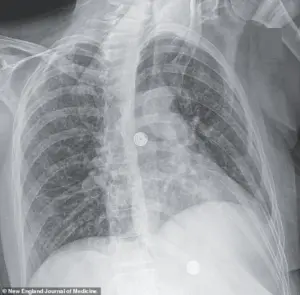

X-ray scans revealed an alarming finding: multiple small nodules scattered across her lungs, a hallmark sign of bacterial infection.

A recent case study highlights this grim reality: a woman’s scans revealed nodules in her lungs, liver, pancreas, and brain, with an enlarged lymph node in her chest.

These findings, though rare, underscore the disease’s potential to evade detection and wreak havoc on multiple organ systems.